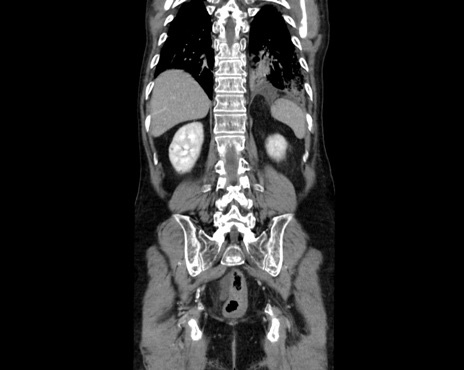

症例26(冠状断像)

【症例】80歳代男性

【主訴】嘔吐

【現病歴】昨晩2回嘔吐あり、今朝になっても嘔吐あり。来院。

【既往歴】胃潰瘍

【身体所見】意識清明、BT 37.6℃、BP 166/95mmHg、HR 100bpm、SpO2 97%、腹部:平坦・軟、腸蠕動音聴取良好、圧痛なし。

【データ】WBC 21900、CRP 1.4